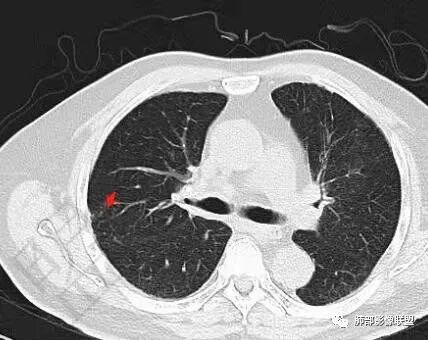

2.影像表现:双肺上叶见结节影及条索影,树丫等,边界可分辨。气管支气管壁广泛增厚、钙化,形态相对均匀一致,上达声门区。支气管膜部受累。增强轻中度强化。纵隔见轻度增大淋巴结。

3.综合分析:双肺上叶病灶较符合继发性肺结核。支气管病变分布具有广泛性、一致性。支气管壁广泛增厚钙化常见于淀粉样变性。累及膜部气管支气管病变的有淀粉样变性和GPA

患者,男,73,间断咳嗽半年,加重半月。双肺底细湿啰音,双下肢轻度水肿。糖尿病、糖尿病微血管病变、慢性肾病、高血压、冠心病、陈旧心梗、冠脉支架、脑梗、慢性胃病史,得全了。吸烟史。血像、ESR增高。胸部CT:气管壁弥漫全层增厚,膜部也受累,气管腔外形仍在、无缩窄,病变延及左右主支气管,纵隔可见肿大淋巴结,大血管壁多发钙化,双肺上叶可见多发树芽,两侧胸膜局限性增厚。考虑:TB?淀粉样变?鉴别GPA、复发性多软骨炎、气管支气管骨化、转移性钙化等。